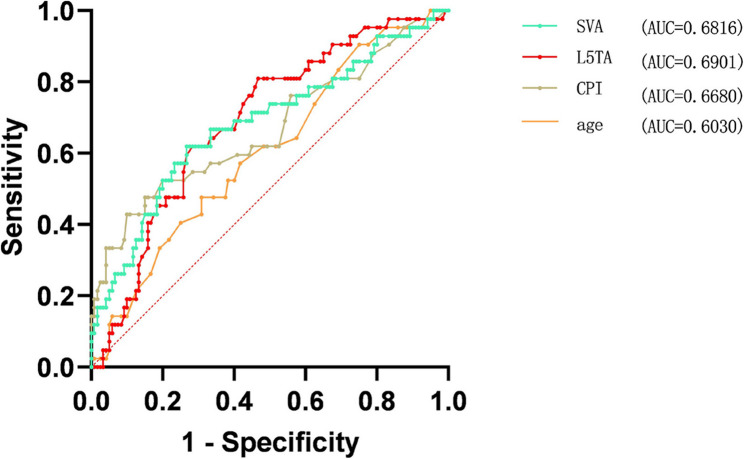

Multivariate binary logistic regression analysis was conducted on the statistically significant variables (collinearity diagnostics confirmed all variance inflation factors were < 5), revealing that Age, L5TA, CPI, and SVA are factors influencing preoperative CIB (p < 0.05) (refer to Table 5, and forest plot demonstrated in Fig. 6). ROC curve analysis revealed the following AUC (Area Under the Curve) values: age (AUC = 0.40), L5TA (AUC = 0.69), SVA (AUC = 0.68), and CPI (AUC = 0.67). The results shown in Fig. 7 indicate that age is a protective factor for CIB. Patients with DS who are under the age of 60.5 are less likely to experience CIB. Additionally, L5TA > 5.75°, CPI > 3.55°, and SVA > 5.305 cm are risk factors for the occurrence of CIB in patients with DS.